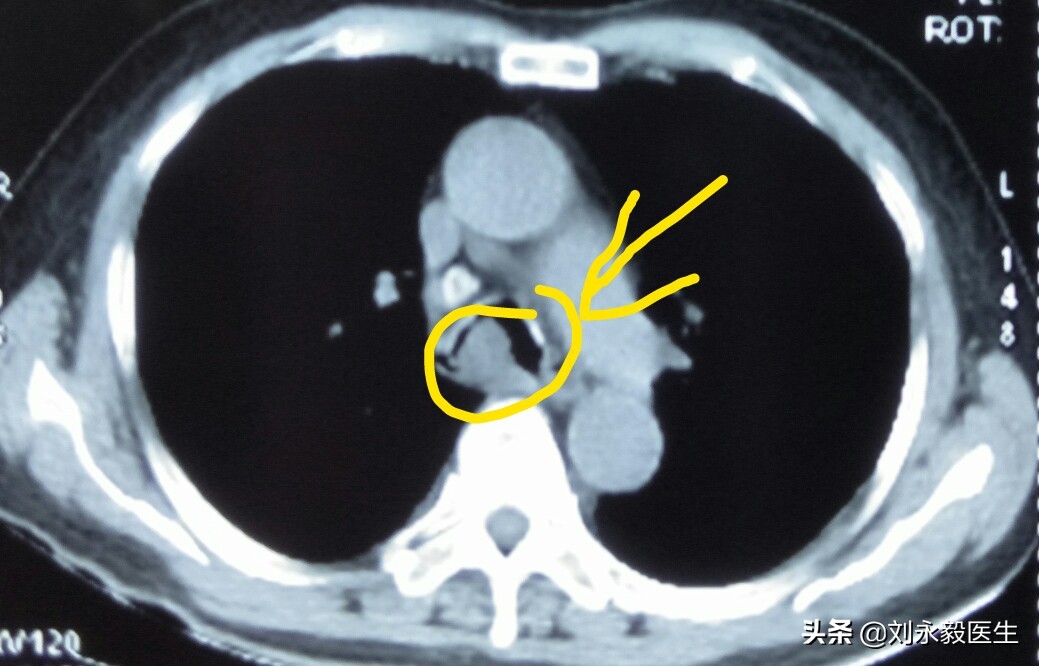

上图是某患者初诊肺癌时的胸部CT,肿瘤不大,如果此时手术,生存时间可能要好很多,很遗憾,采取了“中药化疗”,2018年11月胸闷气短,检查CT发现气管隆突处肿瘤堵塞主支气管,如下CT图。

这时如果给予介入支架等办法,病人有可能还会持续一些时日的,很遗憾病人在憋闷、痛苦中度过了最后半个月。